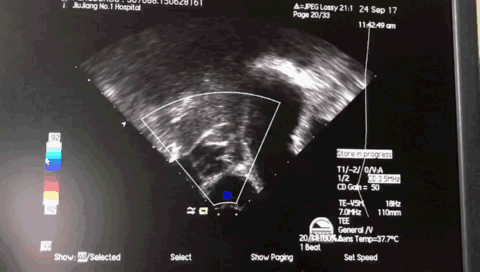

术中超声:

TEE 0:

TEE 45:

TEE 135牵拉试验: